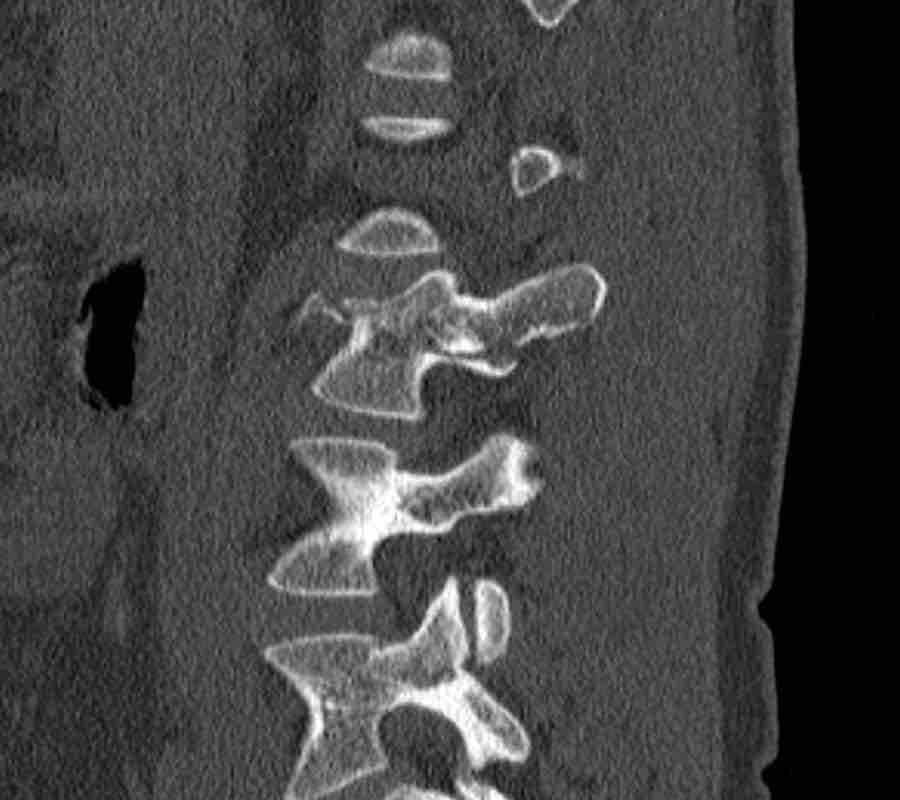

Scroll through the images

Findings:

- Perched facet joints (yellow curved arrows), so think of C injury.

- Posterior displacement of the vertebral bodies in the midline.

- Secondary A4 injury of the vertebral body.

Conclusion

Type C + A4 injury